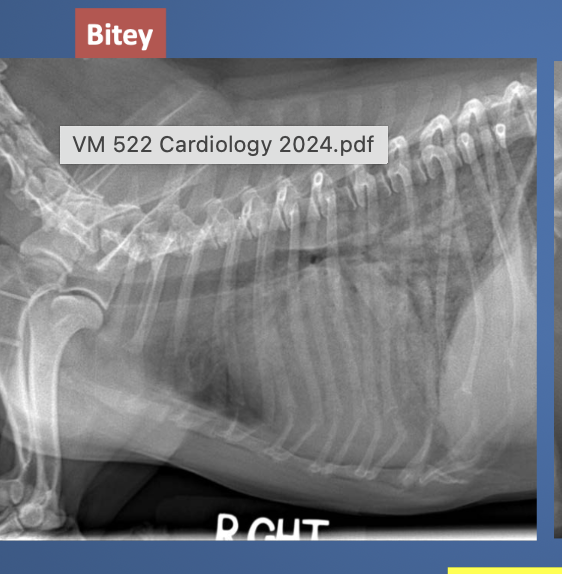

lateral view showed enlarged LA and heart vessels. what is wrong?

DCM. this was lat view